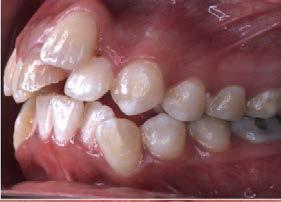

En su análisis facial la paciente presentó un perfil convexo con un tercio inferior aumentado, patrón dolicocefálico severo de VERT, sonrisa gingival e incompetencia labial (Figura 1 A). Durante la exploración intraoral encontramos mordida abierta anterior con apiñamiento severo superior (-13mm) e inferior (-11.5mm), líneas medias desviadas y no coincidentes con la línea media facial, el diente 11

mutilado y con tratamiento de conducto inconcluso, overbite -3mm y overjet 8mm (Figura 1 B).

Extraorales: Frente y perfil. B) Intraorales: oclusales, laterales y sobremordidas.

Figura 1. Fotografías iniciales. A)